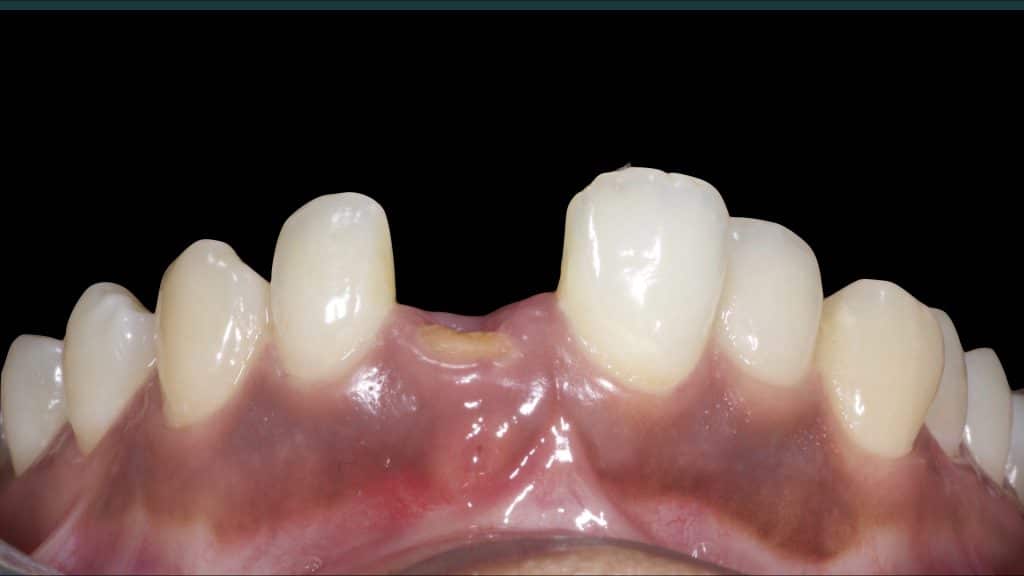

A 27-year female patient with dislodged Resin bonded FPD. She had that FPD for past few years, it had metal wings on palatal surfaces of UR1 and UL2 and a post like metal extension into the root canal of UL1. There was gingival abscess due to fractured root segment most probably due to extended metallic post like structure. Immediate implant placement (IIP) and Immediate restoration (IR) was planned for this patient.

Immediate post-op